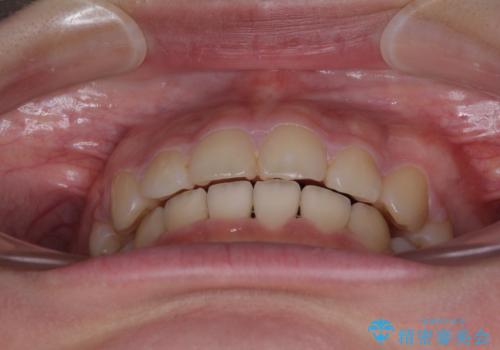

舌の突出癖があり、咬合力も強かったため、治療期間は長くなることが懸念されましたが、舌のトレーニングをしっかりと行っていただいたこともあり、2年弱で治療を終えることができました。